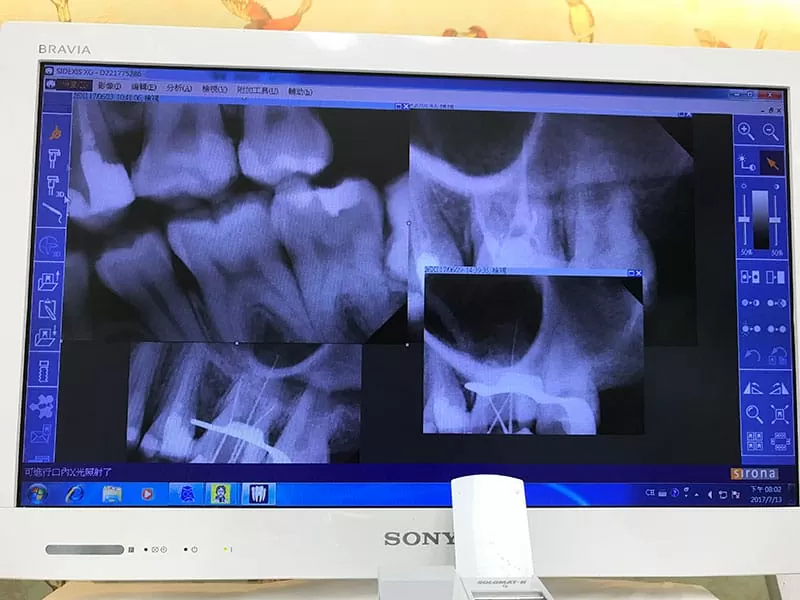

顯微根管治療前,先拍x光片找出病因

施術前詳細的x光

施術處理後 相當乾淨,各個角度都清清楚楚

可以清楚看到完成顯微根管治療的封填狀況,醫師也細心講解了放藥後的狀況,整個顯微根管治療順利結束了! 接下來是轉診牙套部份,整個治療才算圓滿結束~